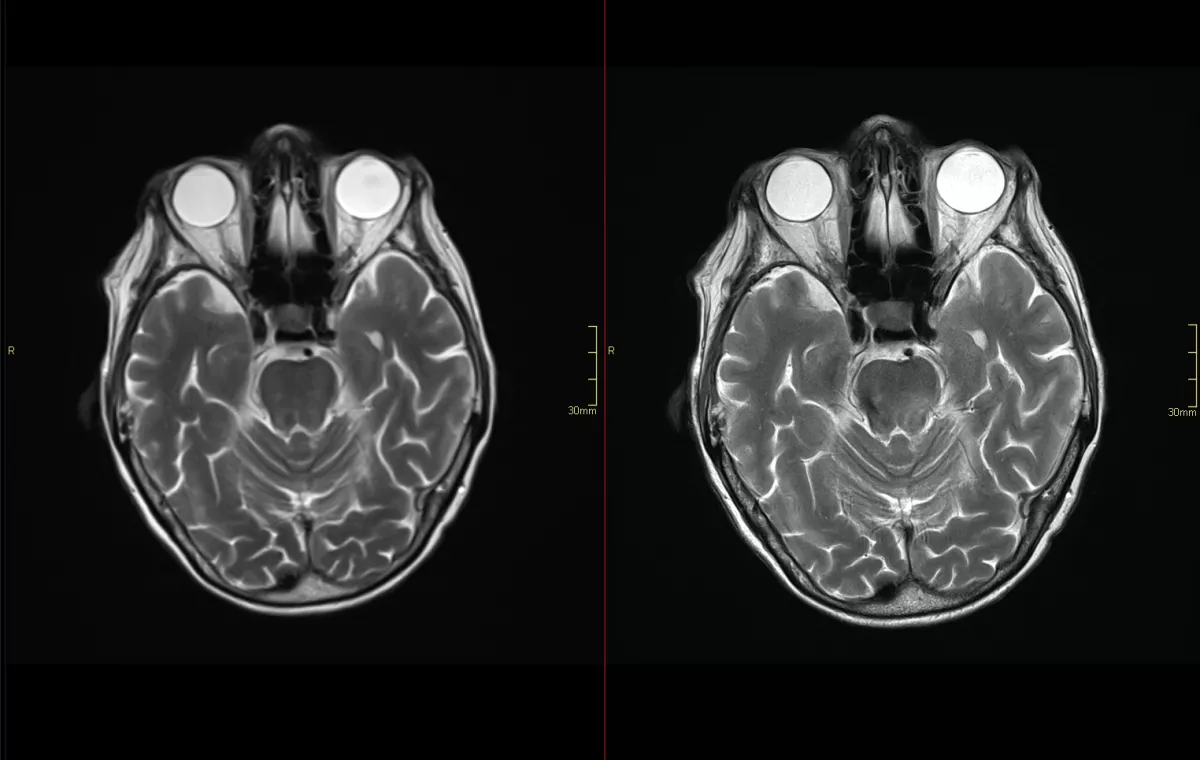

TAVARES, Fla., Sept. 3, 2024 — AdventHealth Waterman is the first hospital in Lake, Volusia and Flagler counties to integrate a groundbreaking artificial intelligence (AI) software, called Deep Resolve Boost, into its Siemens 3T Vida magnetic resonance imaging (MRI) system. This state-of-the-art technology sharpens image quality and cuts MRI scan times by 30-50%, dramatically improving both patient comfort and diagnostic precision.

The AI-powered Deep Resolve Boost technology also significantly reduces blurriness in images, leading to unparalleled diagnostic accuracy.